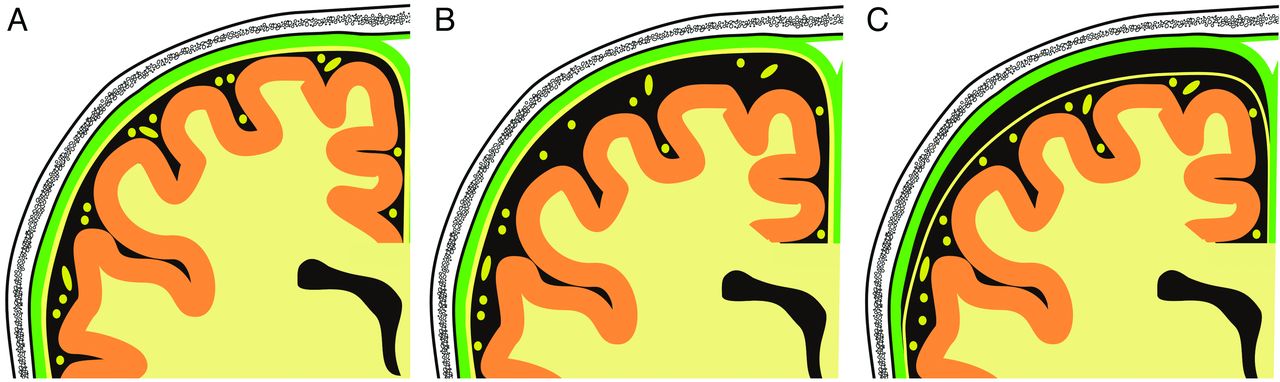

Schematic drawing of the right parietal region as seen in the coronal view imaging. Note the position of the subarachnoid membrane and the subarachnoid vessels (both in yellow). The dura mater is presented in green. A, normal situation; B, enlarged subarachnoid spaces and C, subdural hygroma.

The benign enlargement of the subarachnoid space (BESS) represents an important differential diagnosis for both SDHy and cSDH (Fig 4).48,51,52,90 These subarachnoid fluid collections are frequently observed and often termed confusingly as “benign hygromas of infancy.” BESS probably results from immaturity of the arachnoid villi leading to a transient form of communicating or external hydrocephalus.52 Infants concerned are usually neurologically uneventful without evidence of prior brain injury.91 Nowadays, BESS can clearly be distinguished from SDHy (Fig 5), particularly because of improvements in MR imaging technology. In the presence of BESS, the vessels, which run through the subarachnoid space, are localized away from the brain. On the other hand, in the presence of a subdural fluid collection, the vessels can be found near the surface of the brain.

Benign enlargement of the subarachnoid space. While in CT (A), BESS could be misdiagnosed as SDHy, MR imaging (B, T1-weighted image; C, T2-weighted image) clearly demonstrates the presence of BESS. Note the vessels (thin arrows) spanning through the subarachnoid space. The small black arrows in B point at the subarachnoid membrane.